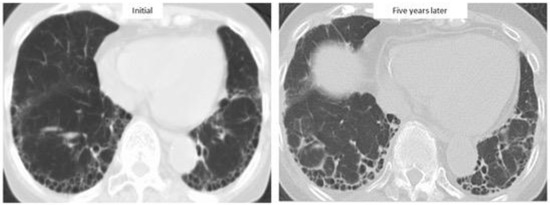

4.2. Disease Behavior

4.3. Predictors of ILD Progression and Prognostic Factors